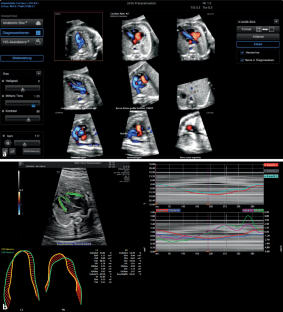

Abb. 1